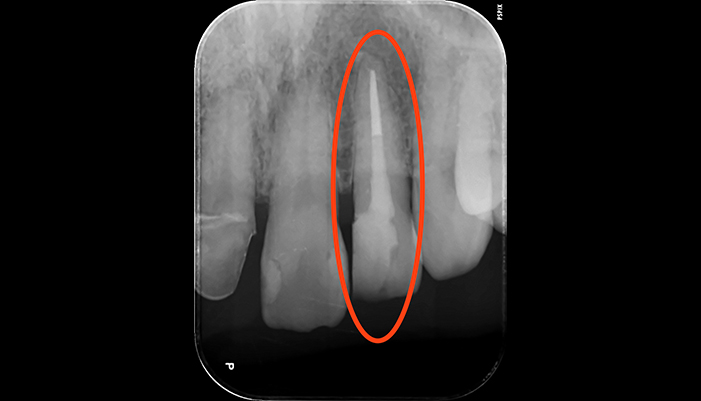

治療前

治療後

| 主訴 | 虫歯がある。根の管が細すぎて見当たらない。 |

|---|---|

| 治療期間 | 1回 |

| 費用 | 再根管治療132,000円(税込)+ ファイバーコア44,000円(税込)= 176,000円(税込) |

| 治療内容 |

ラバーダムを用いて無菌的な環境下で根管治療を行いました。 マイクロスコープ下で虫歯を完全に取り切り、根の管の細さが0.06mm程度になっていたため慎重にNiTiファイルを用いて根管形成を行い、 薬液や超音波器具による洗浄、体に馴染みの良い材質による充填、被せ物を支え、再感染しないように土台を立てました。 |